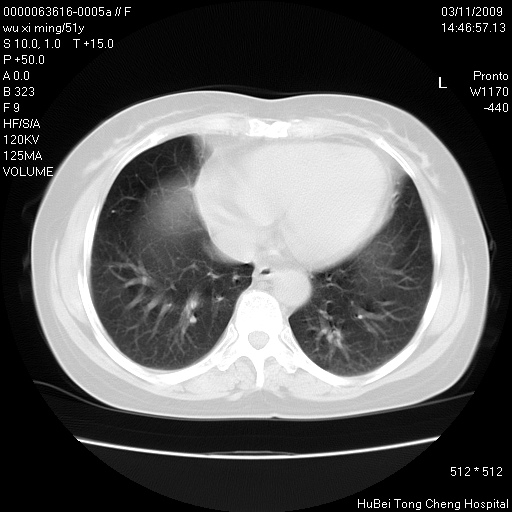

患者 女,51岁。因“胆囊炎,胆囊结石”,行常规术前胸部x线检查发现:右上肺结节病灶,建议行进一步检查。患者无咳嗽、咳痰及咯血等呼吸道症状,近期出现背部疼痛不适。

胸部ct轴位平扫(层厚10mm,螺距1.5,重建间隔10mm;部分层面:层厚3mm,螺距1.0,重建间隔3mm),图像如下:

考虑右肺癌肺内转移!

右肺周围型肺癌伴肺内转移信胸椎转移

1、周围型肺癌。(毛刺正、血管束集征,分叶。)

支持--右肺周围型肺癌---胸椎转移

集束征,胸膜牽拉征,毛刺,淺分葉高度提示ca.

右肺周围型肺癌伴肺内转移及胸椎转移。已无手术机会。